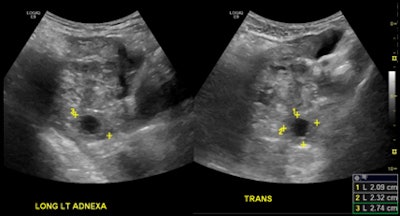

ER-performed ultrasound (top) was interpreted as not having an intrauterine pregnancy. On radiology ultrasound study (above), a radiologist diagnosed an ectopic pregnancy in the left adnexa. All images courtesy of Dr. Myrna Wallace-Severa.The discrepancy differences could be due to a number of factors, including training and experience, according to the researchers. For example, guidelines from the American College of Emergency Physicians (ACEP) for training pathways and the use of bedside ultrasound recommend that residents perform a minimum of 150 bedside ultrasound scans in their residency training to reach competency.